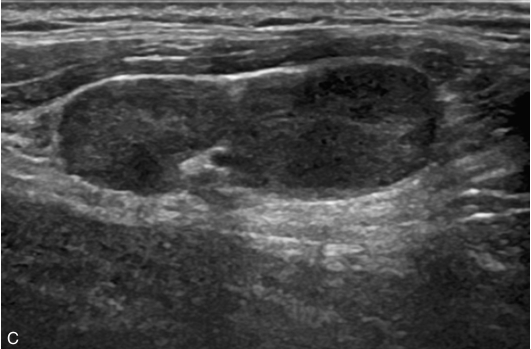

甲状腺右叶中部可见一个肿块,大小约为2.6cm×1.8cm×1.8cm,形状尚规则,边界尚清楚,内部为低回声,分布不均匀,后方回声无变化,CDFI显示肿块内可见丰富的血流信号,见图1-9-1。

图1-9-1 甲状腺髓样癌常规超声图像

A.甲状腺右叶低回声结节纵切面灰阶超声图像;B.甲状腺右叶低回声结节横切面灰阶超声图像;C.CDFI图像